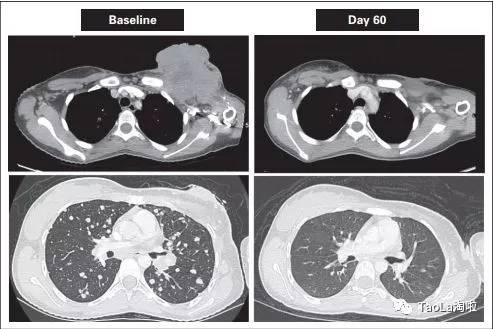

未分化肉瘤

41岁女性

治疗前:患者的肿瘤细胞已广泛转移到肺部,很快要填满肺部了。

治疗后:迅速解决呼吸困难和低氧血症。2个周期后,大部分肿瘤消失,12个周期后,肿瘤组织几乎完全消失!